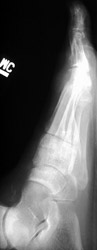

Gout: AP- Erosions 1st MTP joint with tophiGout: AP- Erosions 1st MTP joint with tophiTophaceus Gout: LateralTophaceus Gout: APGOUT is caused by monosodium urate or uric acid crystal deposition within cartilage, bone, or periarticular tissues.

First metatarsophalangeal joint is most commonly affected, followed by the first interphalangeal joint and tarsometatarsal joints. Posterior calcaneal involvement has also been noted. The majority of first presentations are monoarticular. Bilateral and symmetric or asymmetric polyarticular involvement may be present within any of the foot joints.

Acute, episodic soft tissue swelling may represent the earliest radiographic sign. Later, sharp, round or oval marginal joint erosions with sclerotic borders are classically seen with gout. These findings most commonly occur along the dorsum of the foot. Associated soft tissue tophi or intraosseous nodules may be present. "Overhanging margin" occur where the bone resorbs beneath a tophaceous nodule. Joint spaces are usually preserved, but ankylosis may rarely occur with advanced stages of gout. The aforementioned findings may be in different stages of progression with any given patient.